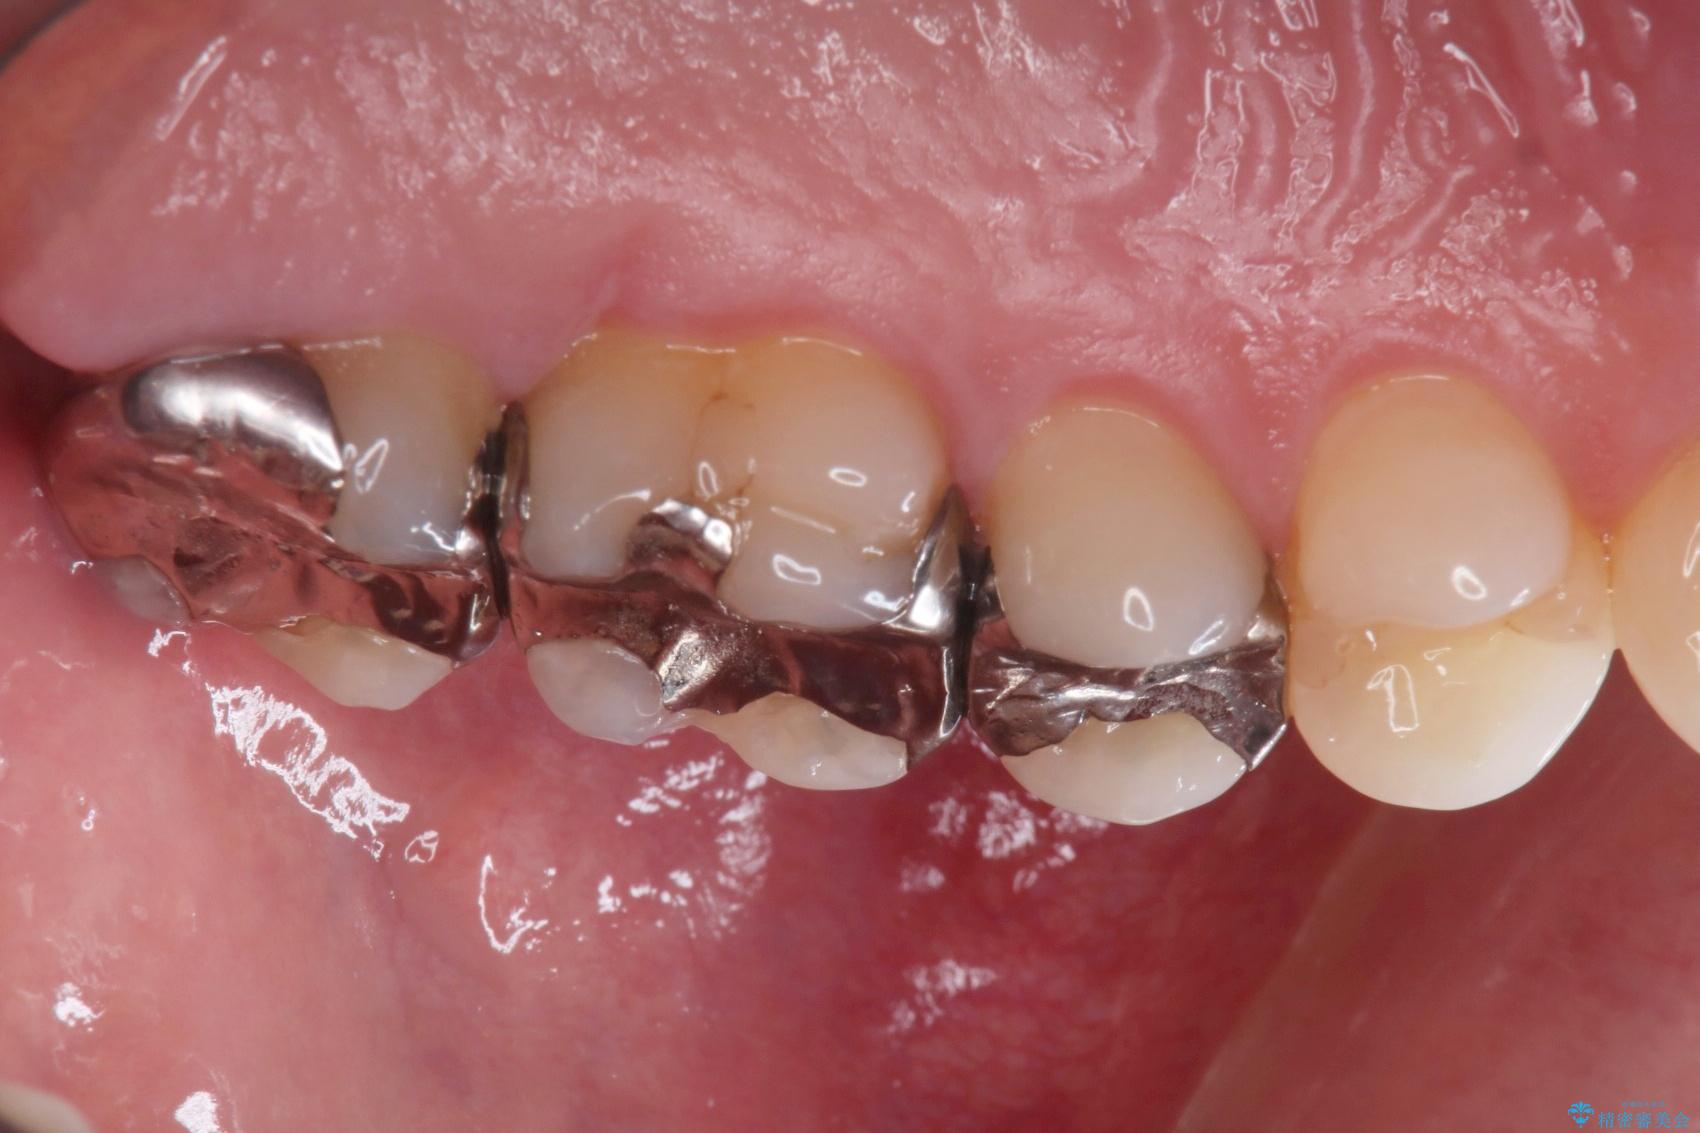

銀歯が綺麗な白い歯になりました。

適合がとてもよいので、フロスの引っかかりも解消されました。

一番奥の歯は銀歯に覆われている範囲が多いため、強度などを踏まえ被せ物にしました。

その他2本は詰め物です。